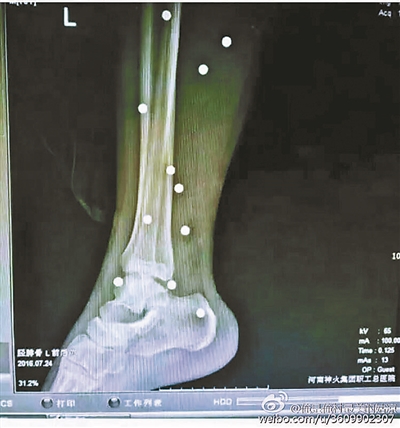

傷者體內(nèi)取出的鋼珠

爆炸導(dǎo)致鋼珠遍布傷者身體各處

黃明的伯伯對(duì)北青報(bào)記者表示,由于黃明直接踩到了爆炸物,所以傷情最為嚴(yán)重,“他的腿被炸斷,身體內(nèi)被炸進(jìn)了40多顆鋼珠。手術(shù)后已經(jīng)從體內(nèi)取出29顆鋼珠,還有十多顆鋼珠沒有取出來(lái)。”根據(jù)黃明的入院記錄,他全身有多處爆炸傷,且全身多處異物存留。

爆炸發(fā)生時(shí),陳浩的位置與黃明靠得很近,因此也受傷較重。他告訴北青報(bào)記者,經(jīng)過10多個(gè)小時(shí)的手術(shù)后,醫(yī)生從他身體里取出了12顆鋼珠。目前,他和黃明兩人經(jīng)過手術(shù)后,已從重癥監(jiān)護(hù)室轉(zhuǎn)至普通病房。其余三人中,陳剛的臀部受傷,當(dāng)天晚上在醫(yī)院清理完傷口后便回了家,而同行的兩名女生身上有一些擦傷。